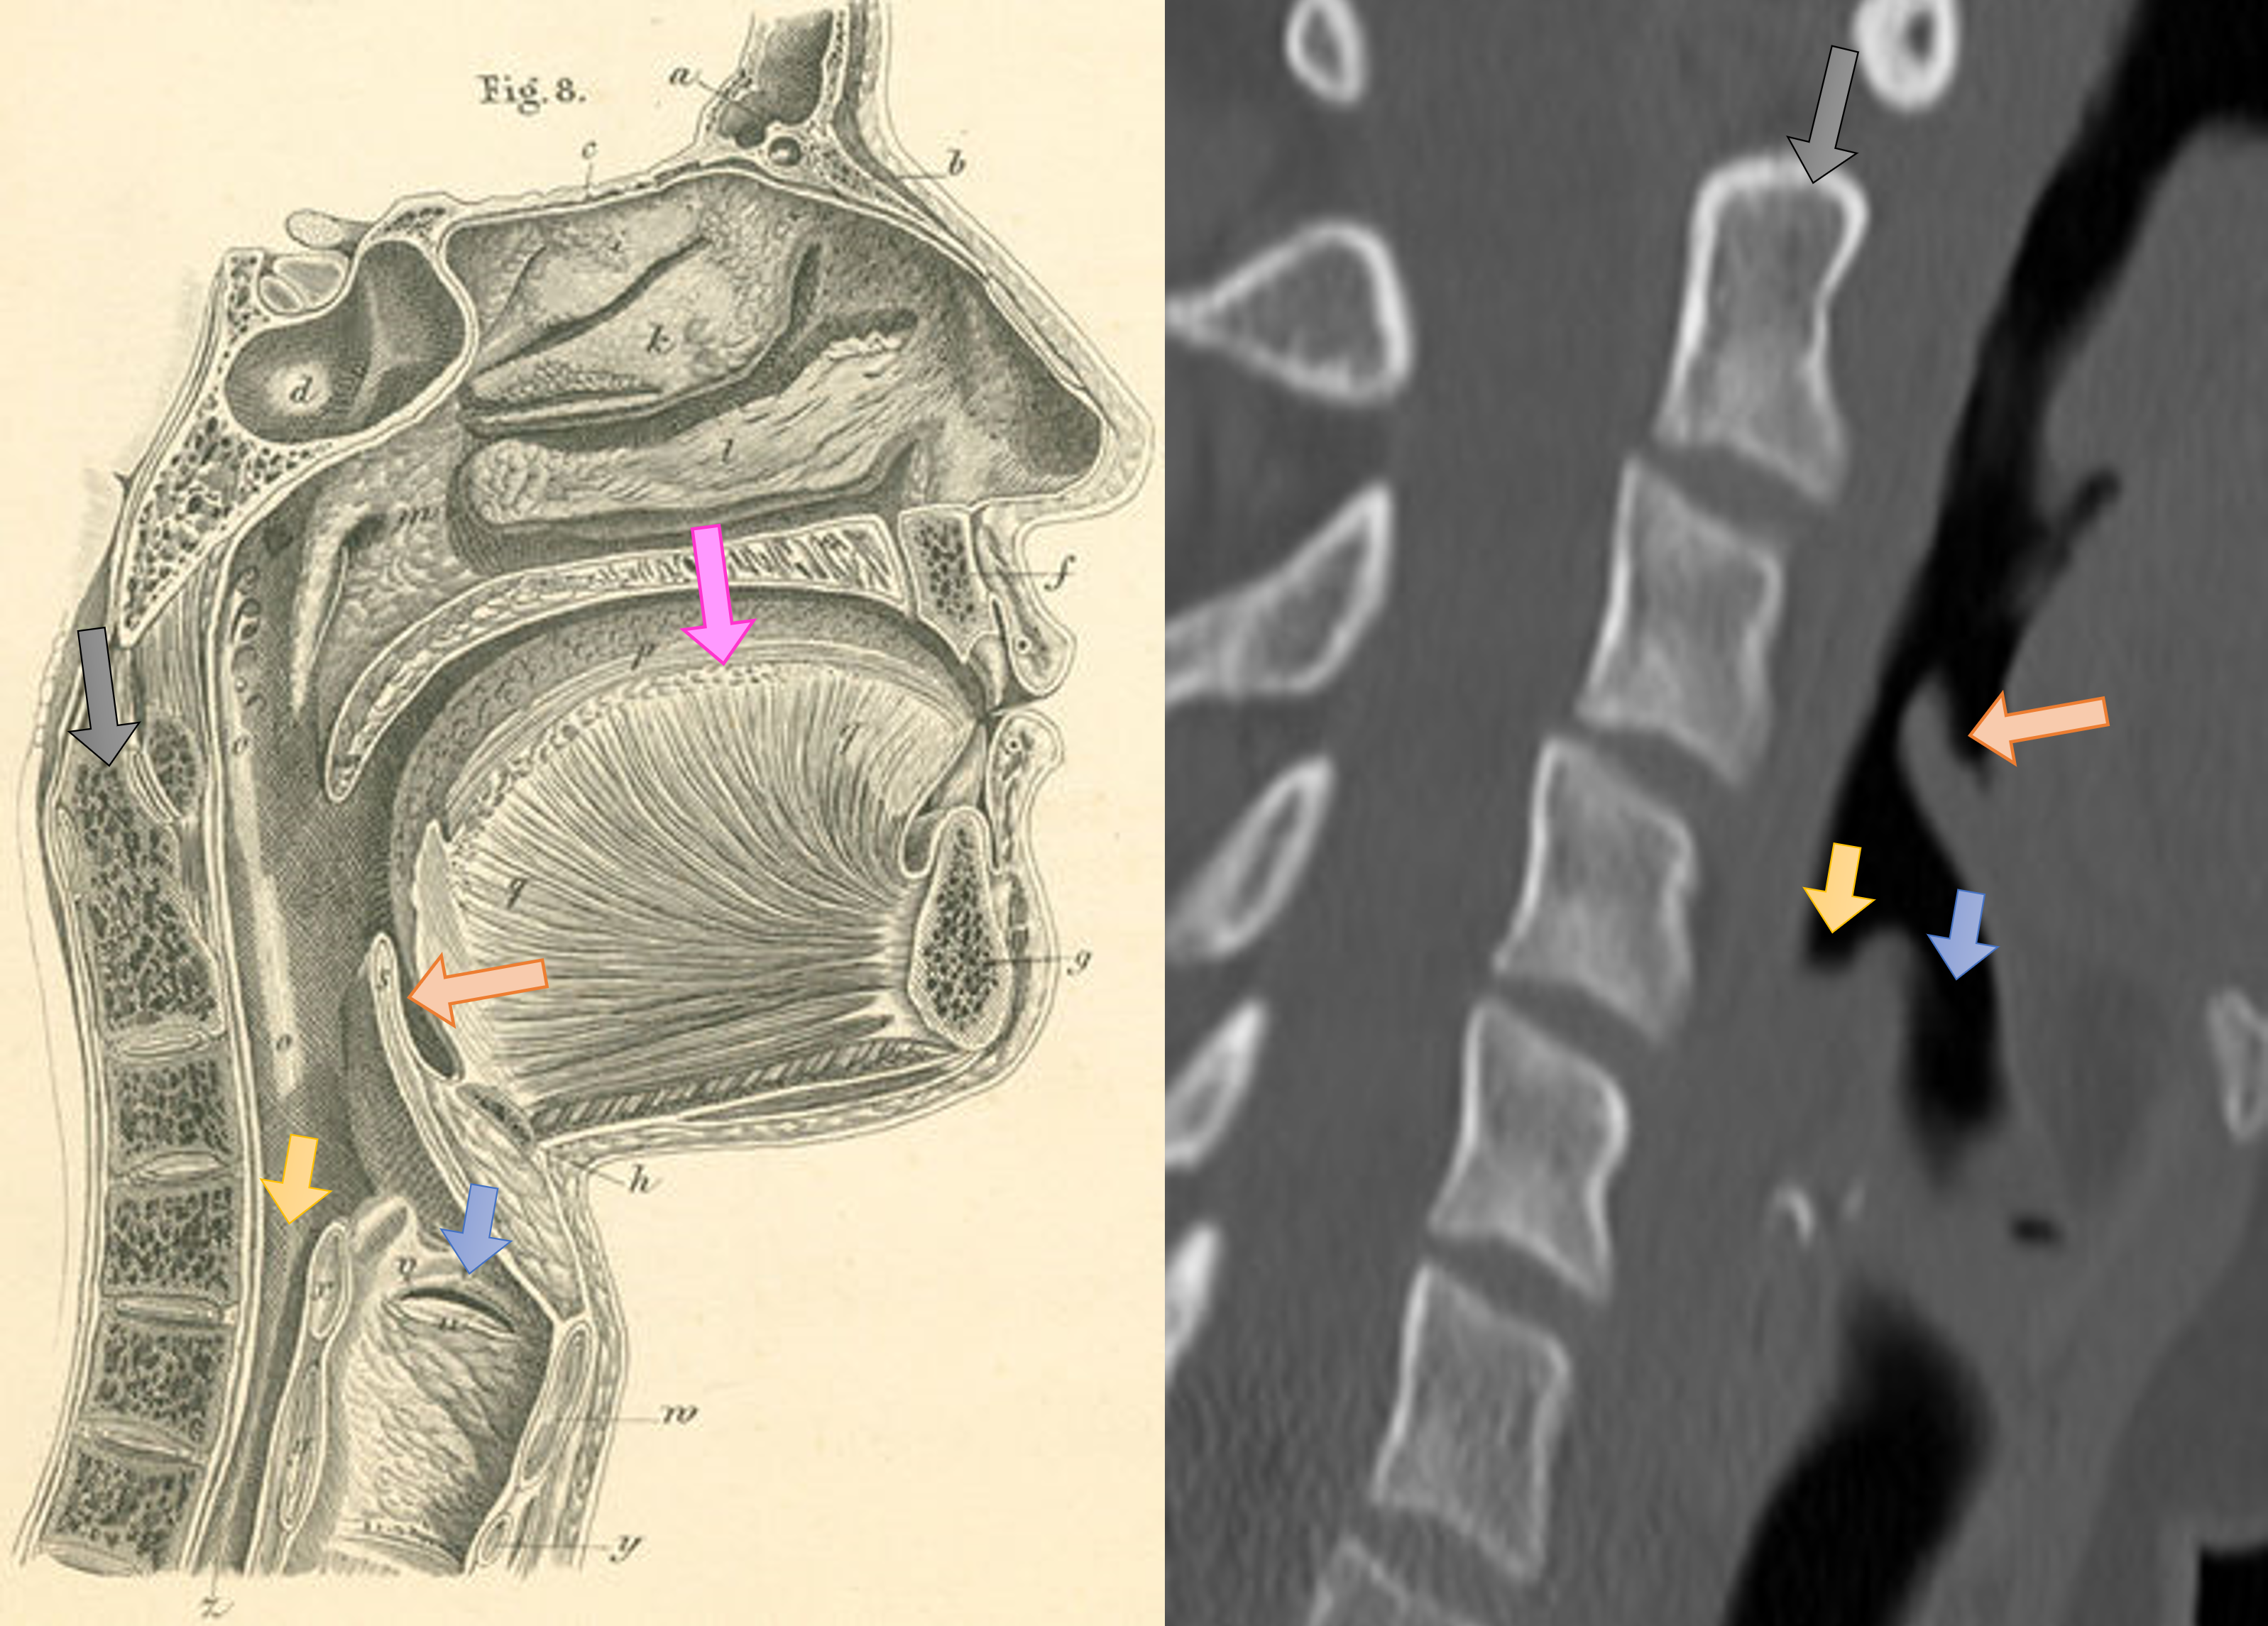

후두경을 사용한 직접 검사로 후두개염을 확진할 수 있지만, 기도 경련을 유발할 수 있어 주의해야 한다.[19] 감염된 후두개는 부어 있으며 "선홍색"을 띤다.[27] 영상 검사는 치료를 지연시킬 수 있으므로 응급 상황에서는 권장되지 않는다.[19]

- 경부 측면 X선 사진: 기도와 후두개, 경부 연부 조직의 형태를 평가한다. X선 사진상 비대한 후두개는 "엄지손가락 인상 징후(thumb sign)", 후두개곡의 소실은 "Vallecula sign"이라고 불린다.

후두경을 사용한 직접 검사로 확진할 수 있지만, 기도 경련을 유발할 수 있으므로 주의해야 한다.[19] 이러한 이유로 설압자를 사용하여 후두개를 관찰하는 것은 권장되지 않는다. 따라서 수술실과 같이 통제된 환경에서 간접 섬유 내시경 검사를 통해 진단한다.[19] 감염된 후두개는 부어 있으며 "선홍색"을 띤다.[27]측면 경추 X-ray에서 엄지손가락 인상 징후는 부어오르고 확대된 후두개를 나타낸다.[10] 그러나 정상적인 X-ray는 진단을 배제하지 않는다.[10] 초음파(초음파 검사)가 도움이 될 수 있지만, (2018년 기준) 연구 초기 단계에 있다.[10]

경부 측면 X선 사진은 기도와 후두개, 경부 연부 조직의 형태를 평가하는데 사용되며, X선 사진상에서 비대한 후두개는 "thumb sign"이라고 불린다.[49] 후두개곡의 소실(Vallecula sign)도 관찰할 수 있다.[50] 크루프와의 감별을 위해 경부 정면 X선 사진도 참고가 된다.